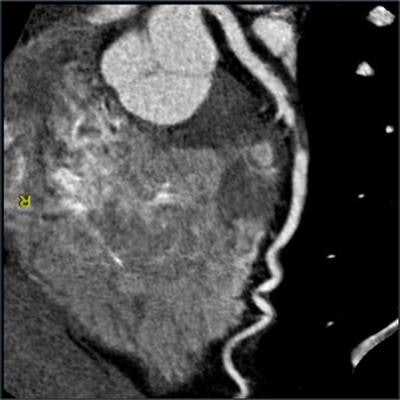

3. Advanced risk stratification

CCTA has the ability to assess the full spectrum of coronary plaque and use this information to stratify a patient's risk of heart disease and cardiac events. On the other hand, stress electrocardiography, stress imaging, and other conventional functional tests are limited to identifying only patients with advanced stenosis.